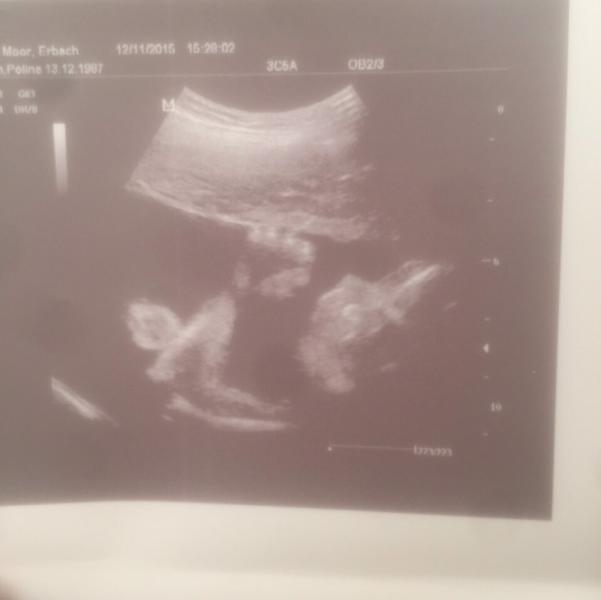

Боже мой сколько радости:))) он такой классный.:) сидим у врача делаем тест на сахар

@kotajk какой снимок хороший. кажется, что ваш малыш из бутылочки пьет ^--^

@dashik2011 верно. после вашего сообщения тоже увидела. просто невероятно

Такие они маленькие милахи!😍😍😍 А наш сегодня спал сладко на файндиагностик😁🙈

@juluetta-wood 😁 тренируется уже